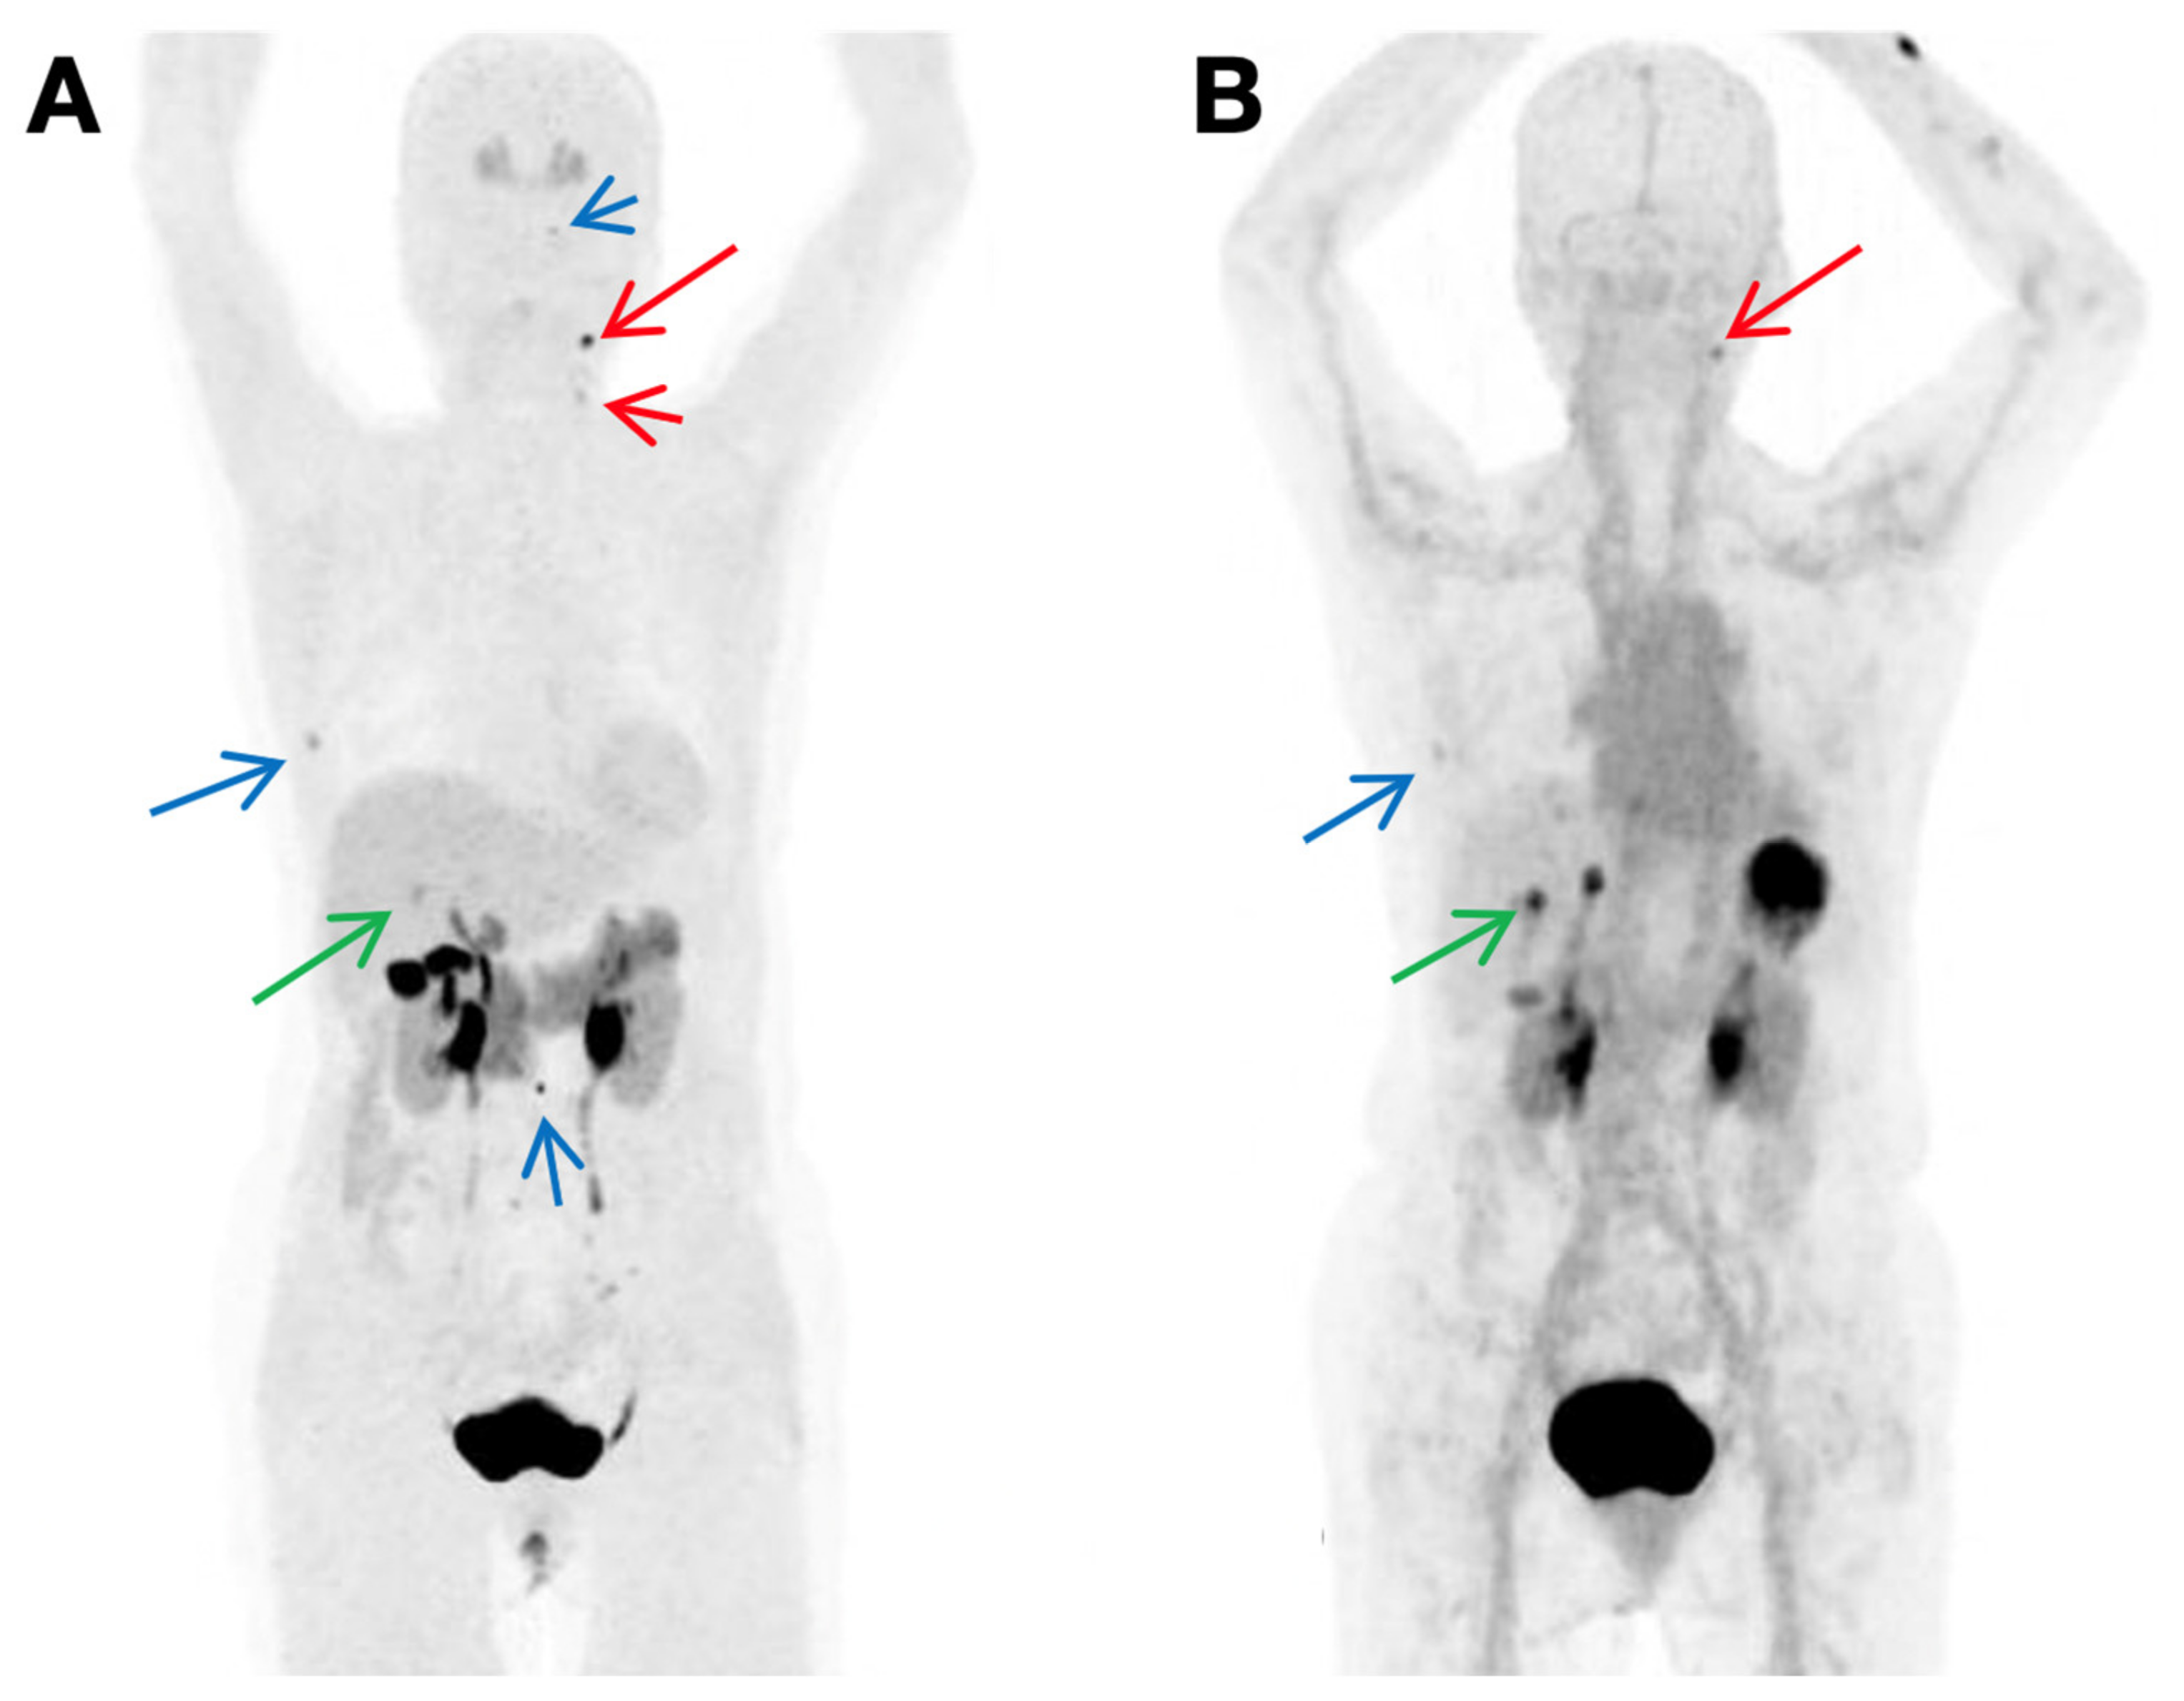

- Bodet-Milin, C.; Faivre-Chauvet, A.; Carlier, T.; Rauscher, A.; Bourgeois, M.; Cerato, E.; Rohmer, V.; Couturier, O.; Drui, D.; Goldenberg, D.M.; et al. Immuno-PET Using Anticarcinoembryonic Antigen Bispecific Antibody and 68Ga-Labeled Peptide in Metastatic Medullary Thyroid Carcinoma: Clinical Optimization of the Pretargeting Parameters in a First-in-Human Trial. J. Nucl. Med. 2016, 57, 1505–1511. [Google Scholar] [CrossRef] [Green Version]

- Bodet-Milin, C.; Bailly, C.; Touchefeu, Y.; Frampas, E.; Bourgeois, M.; Rauscher, A.; Lacoeuille, F.; Drui, D.; Arlicot, N.; Goldenberg, D.M.; et al. Clinical Results in Medullary Thyroid Carcinoma Suggest High Potential of Pretargeted Immuno-PET for Tumor Imaging and Theranostic Approaches. Front. Med. 2019, 6, 124. [Google Scholar] [CrossRef]